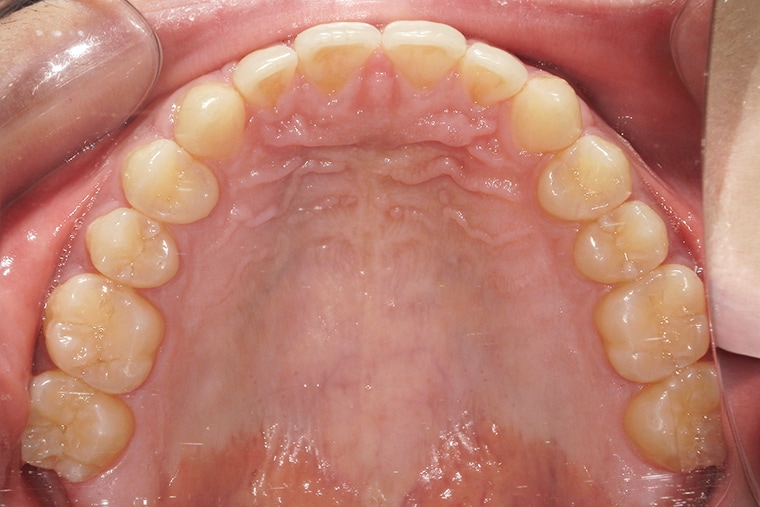

Case Study18歳男性すきっ歯のマウスピース矯正-矯正期間6ヶ月(2024年8月開始)